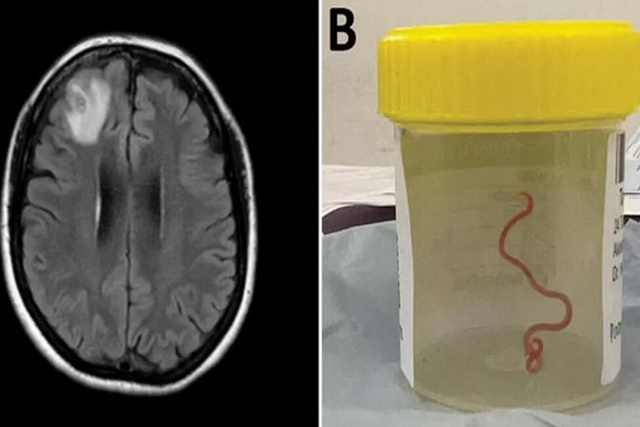

پزشکان برای اولین بار در جهان کرم انگلی هشت سانتی‌متری را از مغز یک زن خارج کردند.

به گزارش سیتنا، وقتی زن ۶۴ ساله استرالیایی برای جراحی مغز به بیمارستان فرستاده شد، جراح مغز و اعصاب، انتظار نداشت که یک کرم گرد انگلی زنده ۸ سانتی متری را از جمجمه او بیرون بکشد.

بر اساس بیانیه مطبوعاتی دانشگاه ملی استرالیا و بیمارستان کانبا، آزمایشات مولکولی تأیید کرد که این کرم Ophidascaris robertsi است، یک کرم گرد که معمولاً در مار پیتون یافت می شود.

سنانایاک که همچنین استاد دانشگاه ملی استرالیا است، می‌گوید: «طبق اطلاعات ما، این اولین موردی است که مغز هر گونه پستانداری، انسان یا غیر آن را درگیر می‌کند».